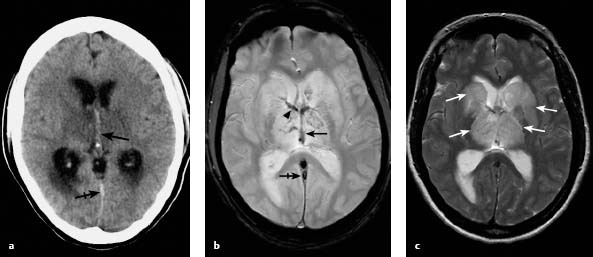

원래 뇌정맥혈전증은 신경과 뇌혈관 클리닉에서 그리 흔한 질환은 아닙니다. 성인에서 1년에 100만 명 당 2-5명 정도입니다. 보통 뇌혈관 질환은 대부분 동맥에서 발생하고, 정맥에서 피가 응고되어 해당 혈액순환이 저하되어 허혈 혹은 출혈이 생기는 정맥혈전증은 드뭅니다. 뇌정맥혈전증이 생기면 피떡도 차있고, 세포괴사로 부종과 뇌출혈 소견도 확인됩니다.

혈전(피떡), 세포 괴사 및 부종, 출혈이 동반된 뇌정맥혈전증 (출처 Radiologykey.com)